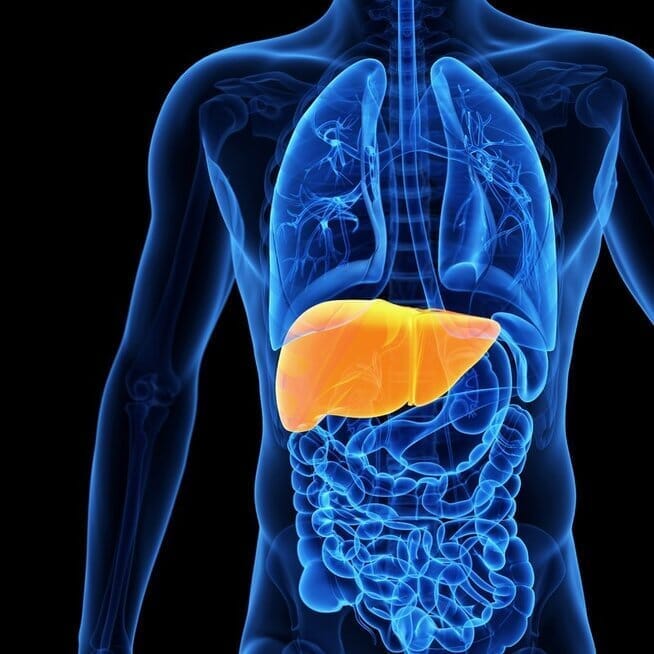

Suriebėjusios kepenys, remiantis Nacionaline sveikatos misija (NHM), yra būklė, kai kepenų ląstelėse kaupiasi riebalų perteklius, rašoma timesofindia.com.

Vienas iš labiausiai pastebimų suriebėjusių kepenų žymenų yra padidėjęs kepenų fermentų, įskaitant ALT ir AST, kiekis laboratoriniuose tyrimuose.

Jie dažnai nepastebimi atliekant įprastinius sveikatos patikrinimus, tačiau teisingai interpretuojant, jie gali būti gyvybiškai svarbūs vertinant kepenų sveikatą.

Laiku atliktas išaiškinimas ir tolesni tyrimai gali padėti anksti diagnozuoti ligą, o tai leidžia imtis intervencijų, tokių kaip svorio metimas, geresnė mityba ir gydymas, siekiant išvengti cirozės ar kepenų nepakankamumo progresavimo.